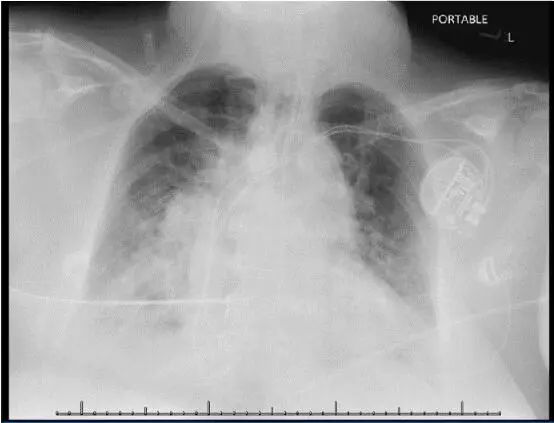

患者T 39.4℃,Bp 150/78 mm Hg。白细胞(WBC)计数14,200/μL,胸片示肺血管充血和右下叶浸润(图1)。

图1